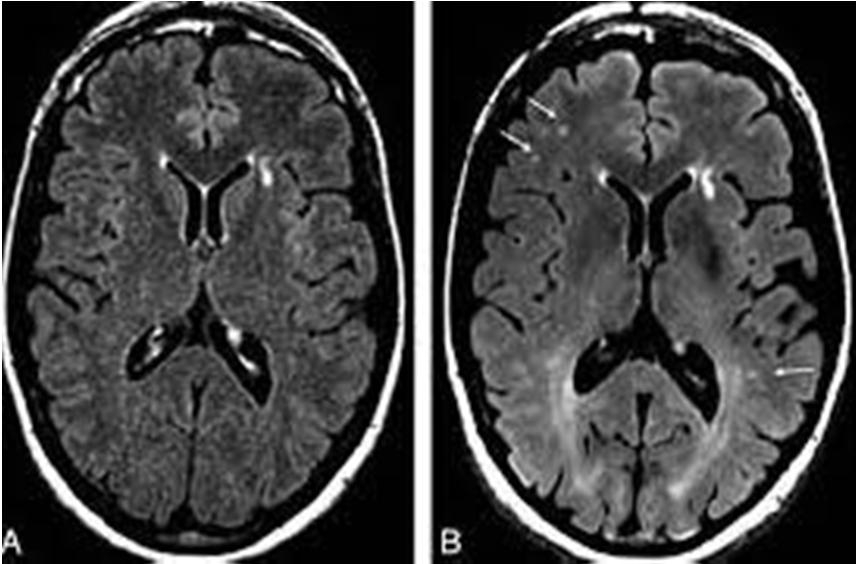

F. Histogram

The histogram of an image generally refers to a histogram of the pixel intensity values. This histogram is a graph that shows the number of pixels in an image at each different intensity value found in that image. The histogram of a digital image with gray levels in the range of [0, L-1] is a discrete function. The histogram technique used on an image mostly represents the comparative frequency of the many gray levels in the image. A histogram is a common tool for improving contrast in medical imaging and other various imaging fields. It recovers the lost contrast by redistributing the image brightness values that unfortunately may generate undesirable artifacts. T histogram techniques apply on input MRI image and result shown in figure

Fig 5 (a) Original image (b) Histogram graph of Fig. 4 (a) (c) Histogram of original images (d) histogram image of fig 4(c) Fig 8 bounding box applied